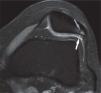

Asimismo, el artefacto por desplazamiento químico se ve reducido mediante el aumento del ancho de banda y mediante la técnica de supresión grasa, quedando bien definida el área de relación entre el cartílago y el hueso subcondral. Con todo ello, encontramos que de manera independiente, tanto el empleo de TR largos, por un lado, como la aplicación de saturación espectral de la grasa, por otro, contribuyen a mejorar el rango dinámico y la RCR. Combinadas ambas técnicas, se consigue en 3.0 T un muy alto contraste fluido-cartílago, de gran importancia para el estudio de posibles lesiones: el efecto artrográfico (figs. 8 y 9).

Imagen coronal en la que se aprecian lesiones profundas en el cartílago articular (flechas grises) y un cuerpo libre (flecha blanca) correspondiente a un fragmento de cartílago desprendido de los espacios señalados con las flechas grises. El alto contraste entre el líquido articular y el cartílago en secuencias ponderadas en densidad protónica con supresión grasa facilita su observación.